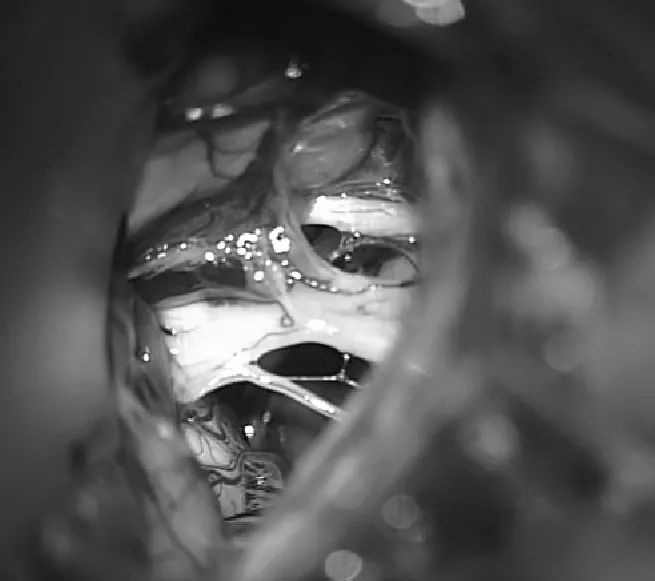

对于这类患者,手术并非简单的囊肿剔除,而是需要在保护重要神经结构和彻底缓解症状之间找到平衡点。Di Rocco教授团队采用的手术策略包括:首先,通过术中神经电生理监测实时评估第七、八对脑神经的功能状态,这使得医生能够在操作过程中随时调整策略,避免进一步伤害。其次,选择恰当的手术入路——通过影像学数据精确定位囊肿与周围神经血管的关系,制定个体化的手术方案。第三,术后的影像学复查(MRI对比)显示,虽然囊肿被成功切除或部分引流,但患者的神经结构和脊液通道得到了明显改善。